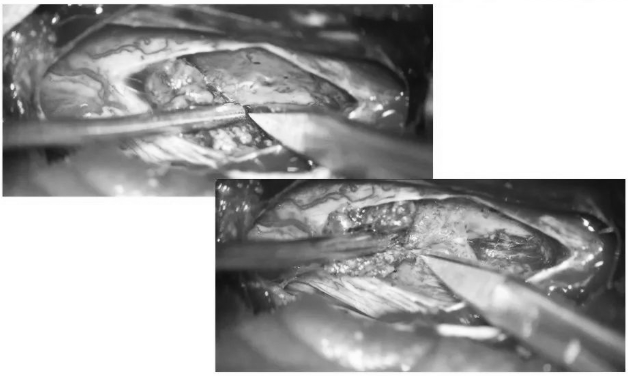

▼测量瘤腔大小,明确肿瘤全切

▼用Proline缝线间断缝合软脊膜,封闭瘤腔,水密缝合硬脊膜